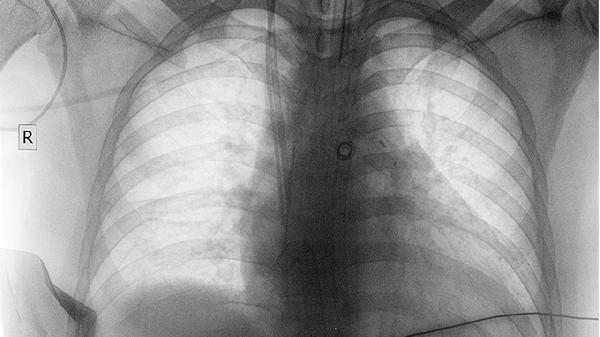

右肺下叶小结节是指在右肺下叶出现的直径小于30毫米的局灶性圆形密度增高影,多数情况下为良性病变,可能与既往感染、炎性假瘤等因素有关,少数情况需警惕早期肺癌等恶性病变。

多数右肺下叶小结节为良性增生,常见于肺部感染后遗留的肉芽肿或局部炎症修复形成的炎性假瘤。这类结节通常边缘光滑、形态规则,在随访观察中可能长期保持稳定甚至缩小。部分良性结节与职业性粉尘接触或真菌感染相关,通过高分辨率CT检查可见钙化或脂肪密度等典型特征。对于稳定的良性小结节,一般建议定期复查胸部CT,无需特殊处理。

部分右肺下叶小结节可能为早期恶性肿瘤表现,尤其当结节呈现分叶状、毛刺征、胸膜牵拉等恶性征象时。这类结节多见于长期吸烟人群或存在家族肺癌史者,随着时间推移可能出现体积增大或密度增高。对于高度可疑的结节,需通过穿刺活检或手术切除明确病理性质,早期干预可显著改善预后。

发现右肺下叶小结节后应根据结节影像特征制定个体化随访方案,8毫米以下无明显恶性特征的结节可间隔6-12个月复查,出现生长性变化的结节应尽早就医。日常生活中需注意戒烟避尘、加强呼吸道防护,保持均衡饮食和适度运动有助于维持肺部健康。若随访期间出现咳嗽咯血、胸痛气促等症状,应立即前往呼吸科或胸外科就诊。